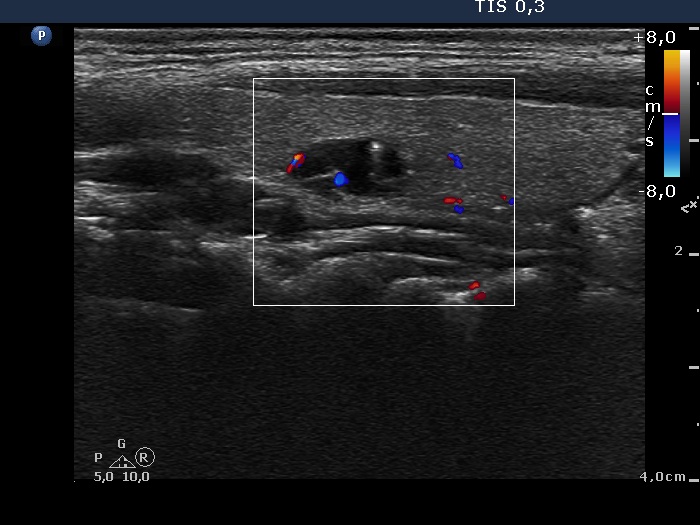

Intranodular hyperechogenic figures - case 402 (ultrasonographic picture 4)

Right lobe, longitudinal view, color Doppler mode. The vascularization is not specific.